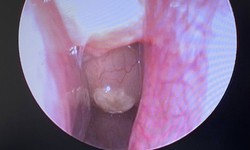

Viêm mũi xoang có cần phẫu thuật không?

Bệnh thường gặp - 10/10/2024 12:41SKĐS - Viêm mũi xoang là một tình trạng phổ biến, xảy ra do nhiễm virus đường hô hấp trên, dị ứng, bất thường giải phẫu mũi xoang hoặc các nguyên nhân khác. Đau xoang, chảy nước mũi và nghẹt mũi là những triệu chứng thường gặp của viêm mũi xoang.

Viêm mũi xoang khi nào cần phẫu thuật?

Bệnh thường gặp - 30/06/2023 10:46SKĐS - Viêm mũi xoang là bệnh lý khá phổ biến tại Việt Nam. Tuy nhiên, hiện nay có nhiều trường hợp bệnh nhân sử dụng các loại thuốc không rõ nguồn gốc để chữa bệnh gây ra nhiều biến chứng ảnh hưởng tới sức khỏe.